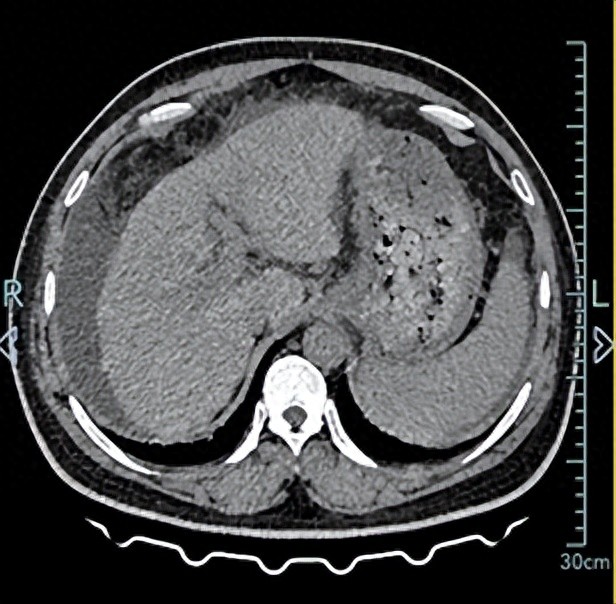

“医生,我这肚子胀了 3 天,吃了肠胃药也没好,弯腰都费劲……”42 岁的陈先生捂着肚子走进杭州市临平区南苑街道社区卫生服务中心曾秋彬医生的诊室,本以为是普通肠胃问题,没想到CT检查后,结果让他慌了神——肝硬化、脾大,门脉高压,腹、盆腔大量积液。

进一步检查后,CT 显示肝硬化、脾大,腹腔已有大量积液——这些都是肝硬化进展的典型信号。